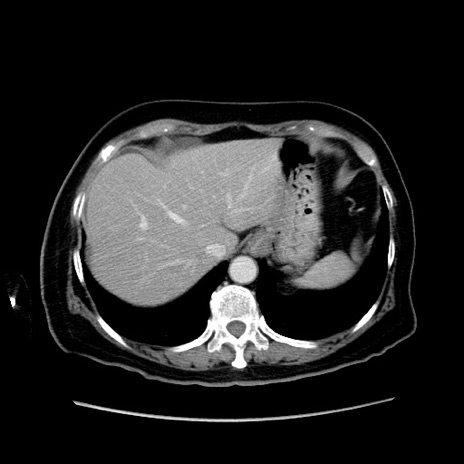

症例19(横断像)

【症例】80歳代女性

【主訴】下腹部痛

【現病歴】約8時間前より下腹部痛の出現あり、救急外来受診。

【既往歴】両側付属器切除

【身体所見】意識清明、下腹部正中に手術痕あり、その部位に一致して圧痛と反跳痛あり。腸蠕動音は亢進。

【データ】WBC 9300、CRP 0.15